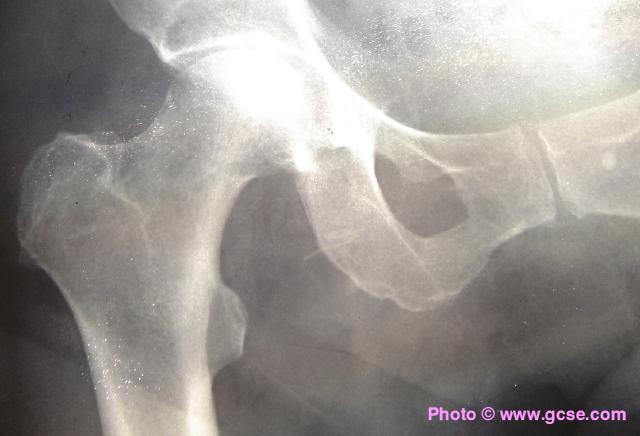

X-ray of healthy human hipX-ray of human hip showing replacement joint

X-rays are absorbed by bone, but pass almost perfectly through flesh. In the image above, the replacement hip joint is made of metal so blocks the passage of X-rays.